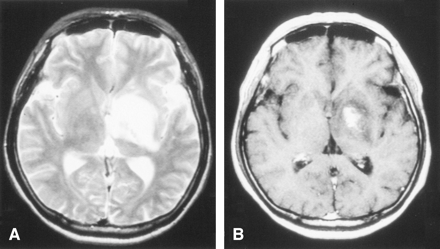

After admission, his consciousness gradually decreased. A head CT scan revealed a mass lesion at the left basal ganglia extending to the ventral site of the midbrain, causing compression to the surrounding tissue with cerebral edema. This lesion showed high intensity on the T2-weighted MR image, which exhibited a contrast effect of gadolinium (Fig 1A,-B).

The diagnostic brain imaging on admission (obtained on January 3, 2002).

A, T2-weighted MR images (TR/TE, 4500/105) show a high-intensity area with a mild mass effect from the left basal ganglia to ventral site of midbrain.

B, Postcontrast T1-weighted images (TR/TE, 500/15). One part of the left basal ganglia shows a enhancement lesion.